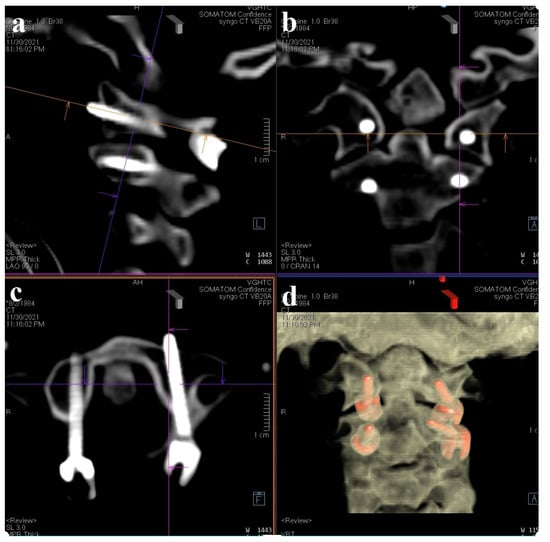

A 37-year-old female with no prior medical history or spinal surgeries presented to our neurosurgery outpatient department five months after a motorcycle traffic accident. Initially diagnosed with a C2 fracture at a local emergency department, she received only conservative treatment and wore a neck collar. Subsequent to the accident, she experienced persistent neck pain radiating to both shoulders and upper back, right-hand numbness with associated weakness, headaches, neck stiffness, and an unsteady gait. An initial cervical spine X-ray revealed the asymmetric widening of the distance between the right C1 arch and the dens with suspected atlantoaxial subluxation (Figure 1). Computed tomography revealed non-fused bony elements (Figure 2). Further cervical spine magnetic resonance imaging (MRI) (Figure 3) highlighted os odontoideum with C1-C2 subluxation and slight spinal cord atrophy at the C1-C2 level due to instability. There was also evidence of ventral compression at the C1-C2 level from chronic inflammatory pannus and granulation tissue.

Figure 2. Cervical spine CT bone window images. The sagittal view and coronal view revealed the non-fused C2 bony elements of the odontoid process.